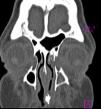

Se manejó superficie ocular con antibiótico tópico de amplio espectro en el ojo izquierdo y lubricante sin conservador en ambos ojos. Se interconsulta al servicio de genética, quien hace el diagnóstico de síndrome de EEC. Resuelto el cuadro infeccioso, se realiza exploración de vía lagrimal bajo anestesia, encontrando vía lagrimal derecha con obstrucción ósea a un nivel aproximado de la unión de saco con conducto nasolagrimal y vía lagrimal izquierda permeable con trayecto sinuoso. La tomografía axial computarizada demuestra la obstrucción ósea del conducto nasolagrimal derecho (fig. 6) y una pérdida de la solución de continuidad a nivel de la pared medial del saco lagrimal izquierdo que comunica con las celdillas etmoidales y la cavidad nasal, formando una falsa vía. Se optó por manejo conservador y vigilancia, y se planea realizar una dacriocistorrinostomía bilateral al lograr un mayor crecimiento mediofacial a una edad mayor.